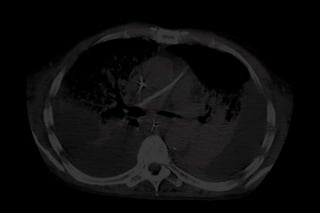

CLASSIFICAÇÃO SEGUNDO

A MORFOLOGIA PULMONAR

Grupo HD

(Hiperdensidades Difusas):

Hiperdensidades   difusas     e

não delimitadas por estrutura

anatômica;

Gusman P.B., 2000